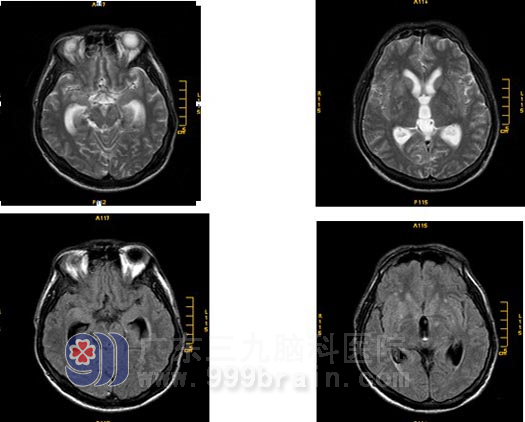

影像学表现

平扫: 双侧基底节区及双侧大脑半球皮层下白质内多发病灶,幕上轻度梗阻性脑积水。

增强扫描:基底池、桥前池及双侧外侧裂池软脑膜均可见明显强化;桥脑、小脑及双侧大脑半球可见散在的斑点状异常强化灶